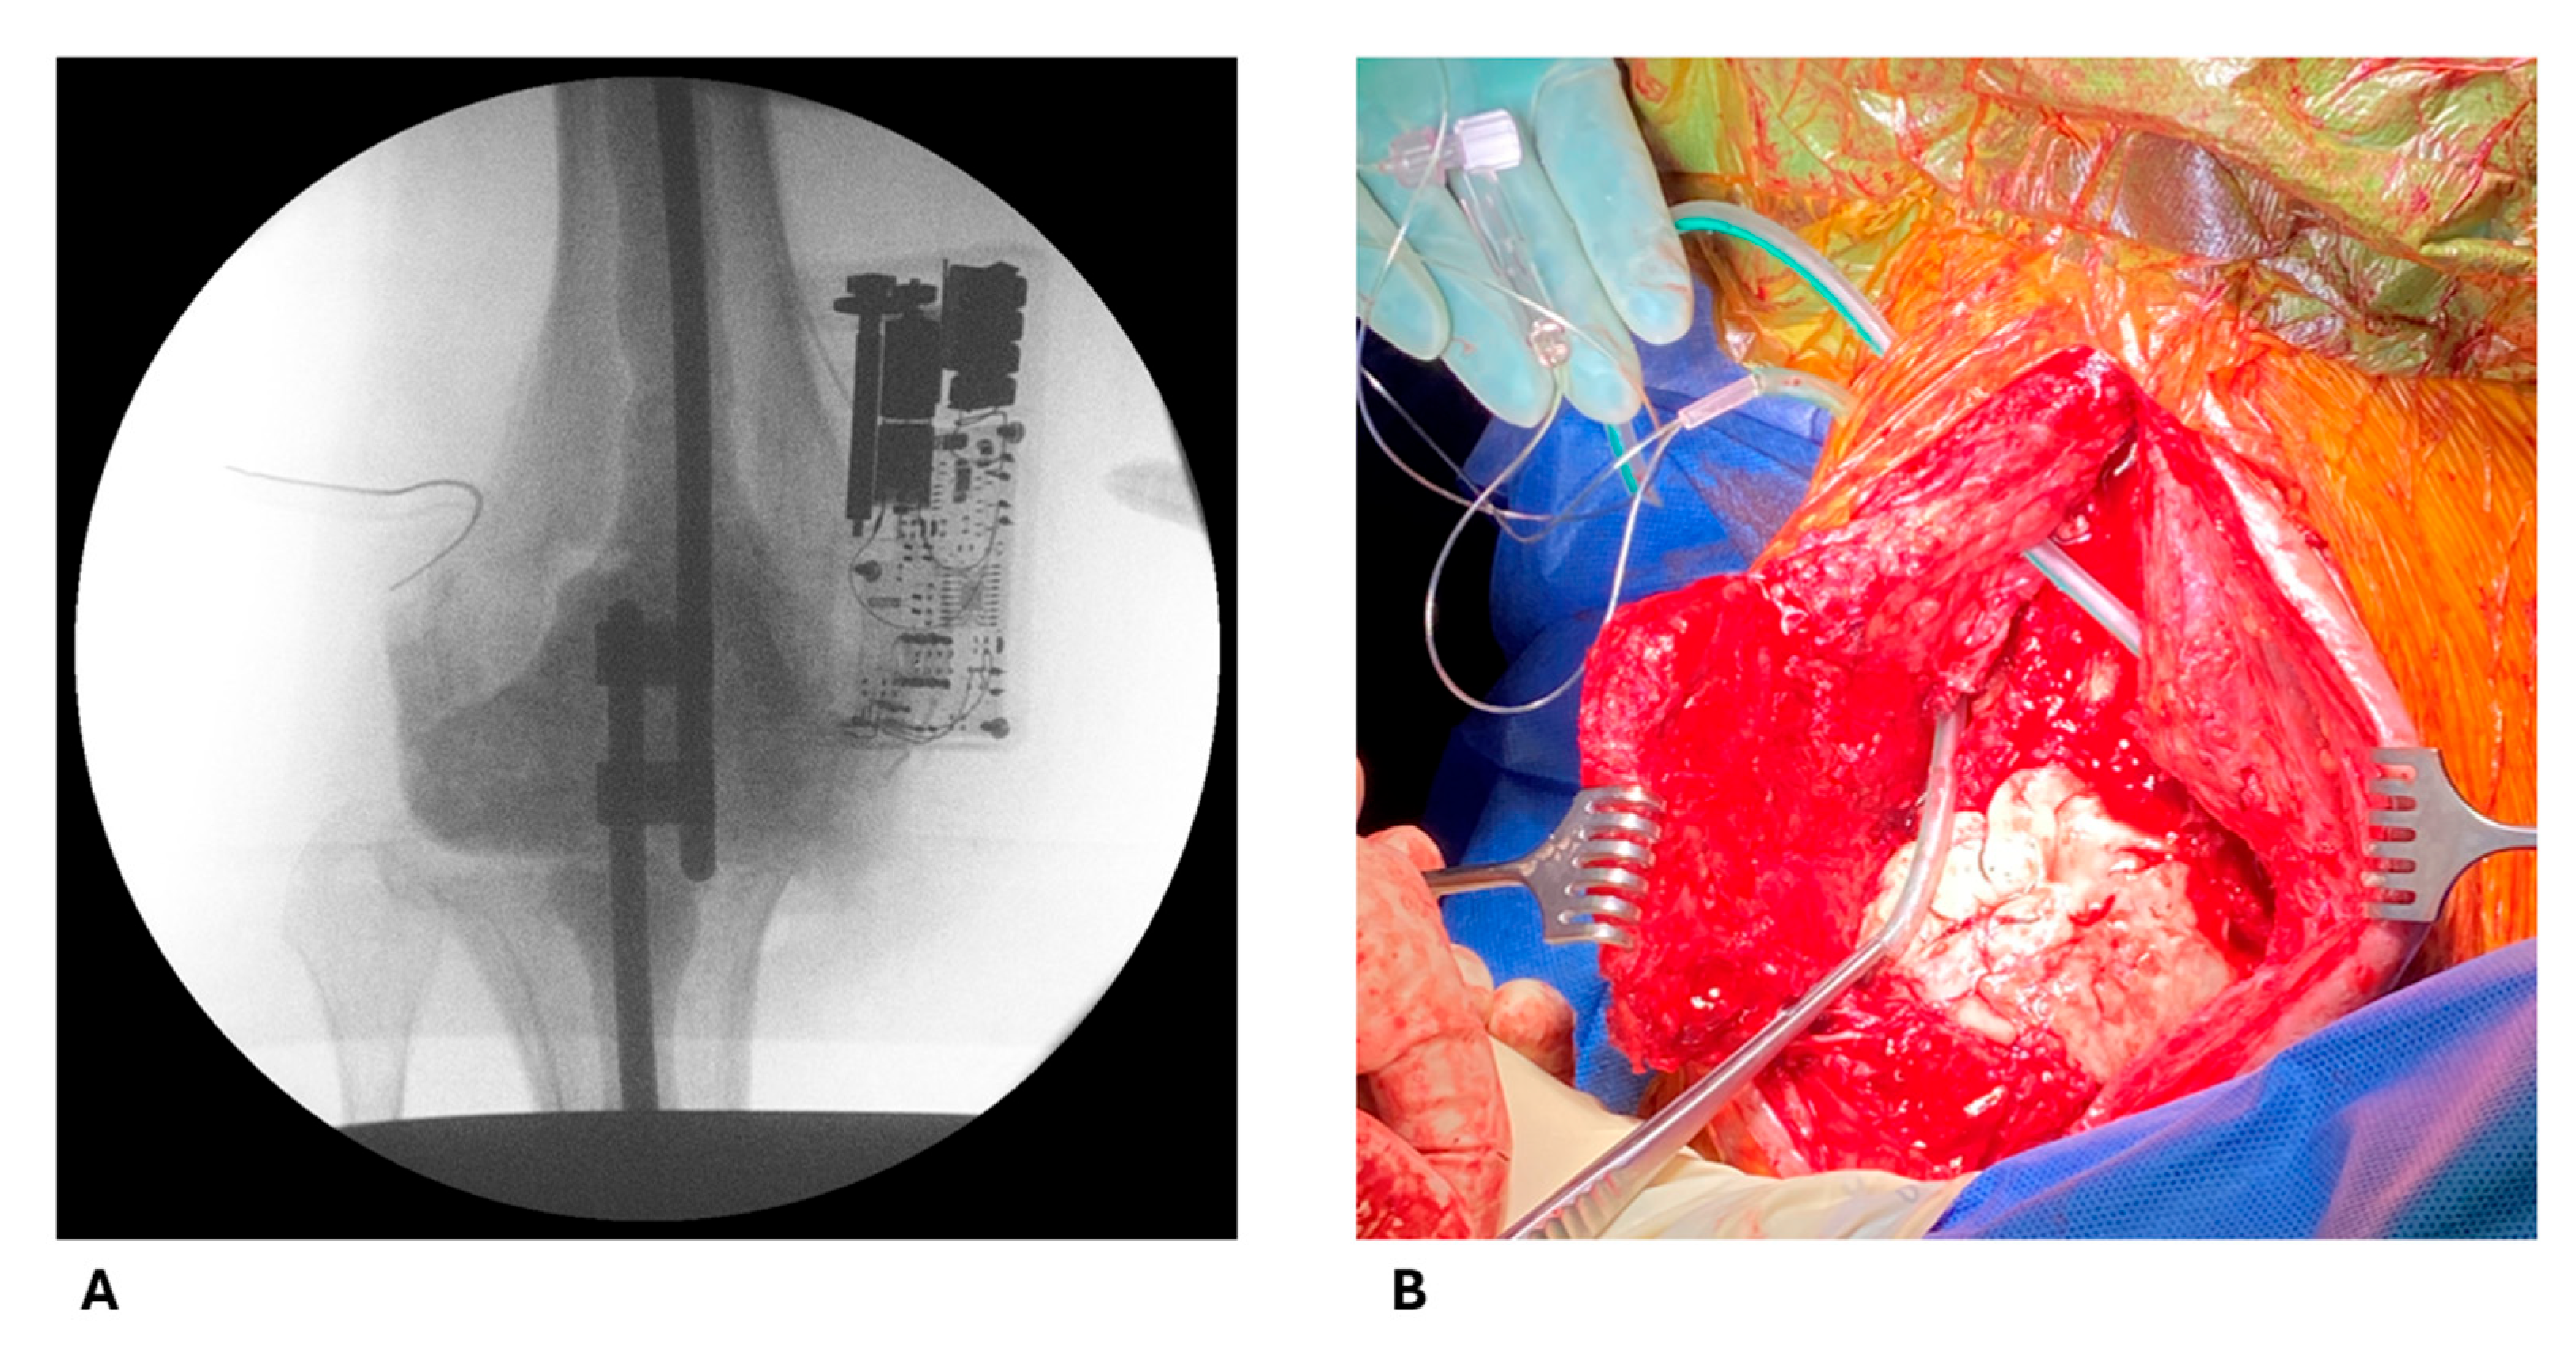

4.2. Intraoperative Procedures